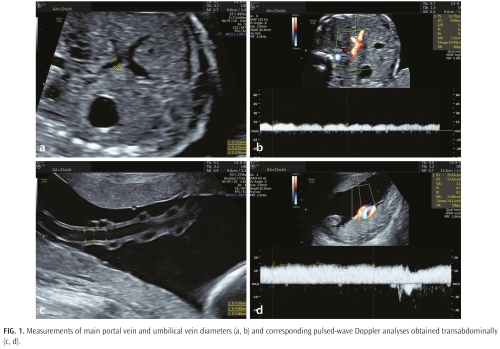

Görkem Arıca, İsmail Yılmaz, Doğu Küçüksüleymanoğlu, et al.

Arıca et al. reported that in fetuses with fetal growth restriction, decreased umbilical venous perfusion is accompanied by a compensatory increase in main portal vein flow, whereas the type of umbilicoportal anastomosis does not significantly affect main portal vein hemodynamics.